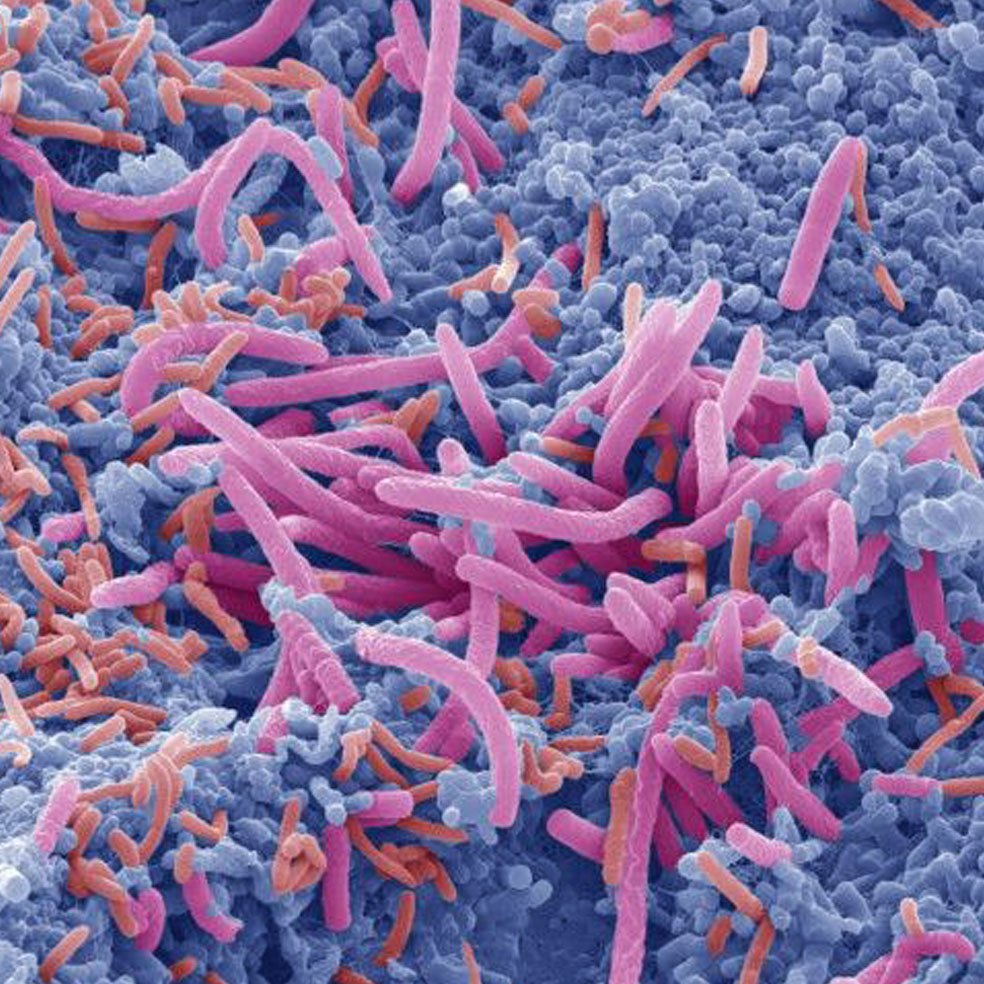

La tiña es, en todo caso, apenas un ejemplo de los microbios que nos acechan. Nuestro cuerpo funciona, al fin y al cabo, como un ecosistema andante con una desmesurada –y muy inquietante– capacidad de atracción para parásitos, bacterias y demás aprovechados de un mundo mayormente microscópico. Por si tiene dudas, agárrese: en nuestro interior habita una cantidad de microorganismos 15.000 veces mayor que toda la población de la Tierra. Y, ojo, mejor no abra la boca de asombro porque dejará al descubierto los más de 500 tipos de bacterias que residen en ella.

La piel puede albergar cerca de un billón de microorganismos. Algunos tienen una presencia temporal en células cercanas a glándulas sebáceas, e incapaces de reproducirse, mueren al cabo de unas horas. Otras bacterias residentes, como la Staphylococcus epidermidis, metabolizan sudor, sebo y producen el olor.